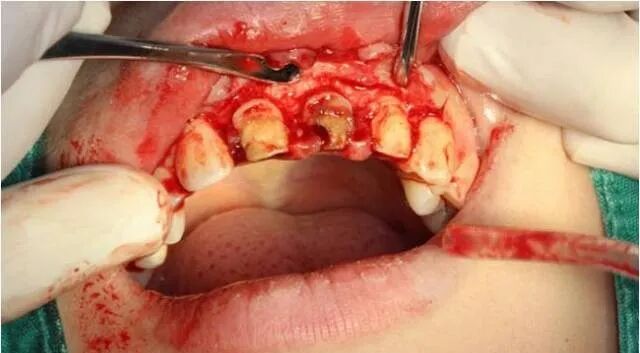

颈缘骨修整